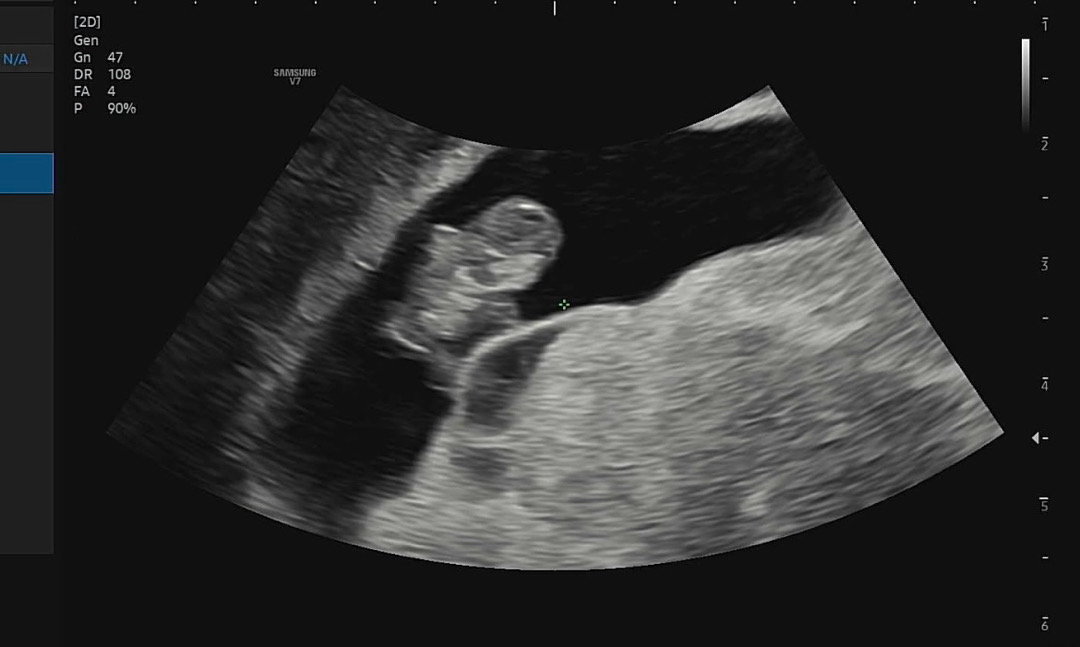

워낙 자궁경부가 약해서 결혼전에도 피가 자주 비치곤했는데 임신 초기부터 피가 살짝살짝 비쳐서 첫째때 너무 놀라 병원자주갔었어요. 그래도 초기에만 그러고 아이한테는 이상이 없어 지금은 아주 건강한 4살이되었어요. 첫째때 경험이 있어 이번에도 피가 비쳤지만 대소롭지 않게 생각하고 병원가서 질정 처방 받고 유산방지주사까지 맞고왔는데 일주일동안 피비침이 없다가 어제 저녁 왈칵 핏덩어리가 나오길래 너무 놀라서 잘못되면 어떻하나 걱정했어요. 전날에 갑자기 입덧이 괜찮아서 더 걱정이 들었던것 같아요ㅠ 자고 일어나 오늘 아침 동네 산부인과중 빨리 문여는 곳 가서 초음파 보고왔어요ㅠ 진료 대기하는 동안 떨려서 눈물이 나올뻔한걸 겨우 참았어요. 진료 받을때 설명 드리니 너무 걱정말라고 괜찮을거란 선생님 말에 안심하고 초음파 봤는데 젤리곰이 딱! 보이는거에요ㅠㅠ 심장소리도 좋고 주수대로 잘 크고 있다고 하셨어요. 너무 걱정됬는데 얼마나 다행이던지ㅠ 남편이랑 진료 끝나고 기뻐서 울었네요ㅠㅠ 그래도 혹시 모르니 안정기 될때까지 무리하지말아야 겠어요. 혹시 저와 같은 일을 격으신 분이 있다면 제 글이 도움이 될까해 올려요~